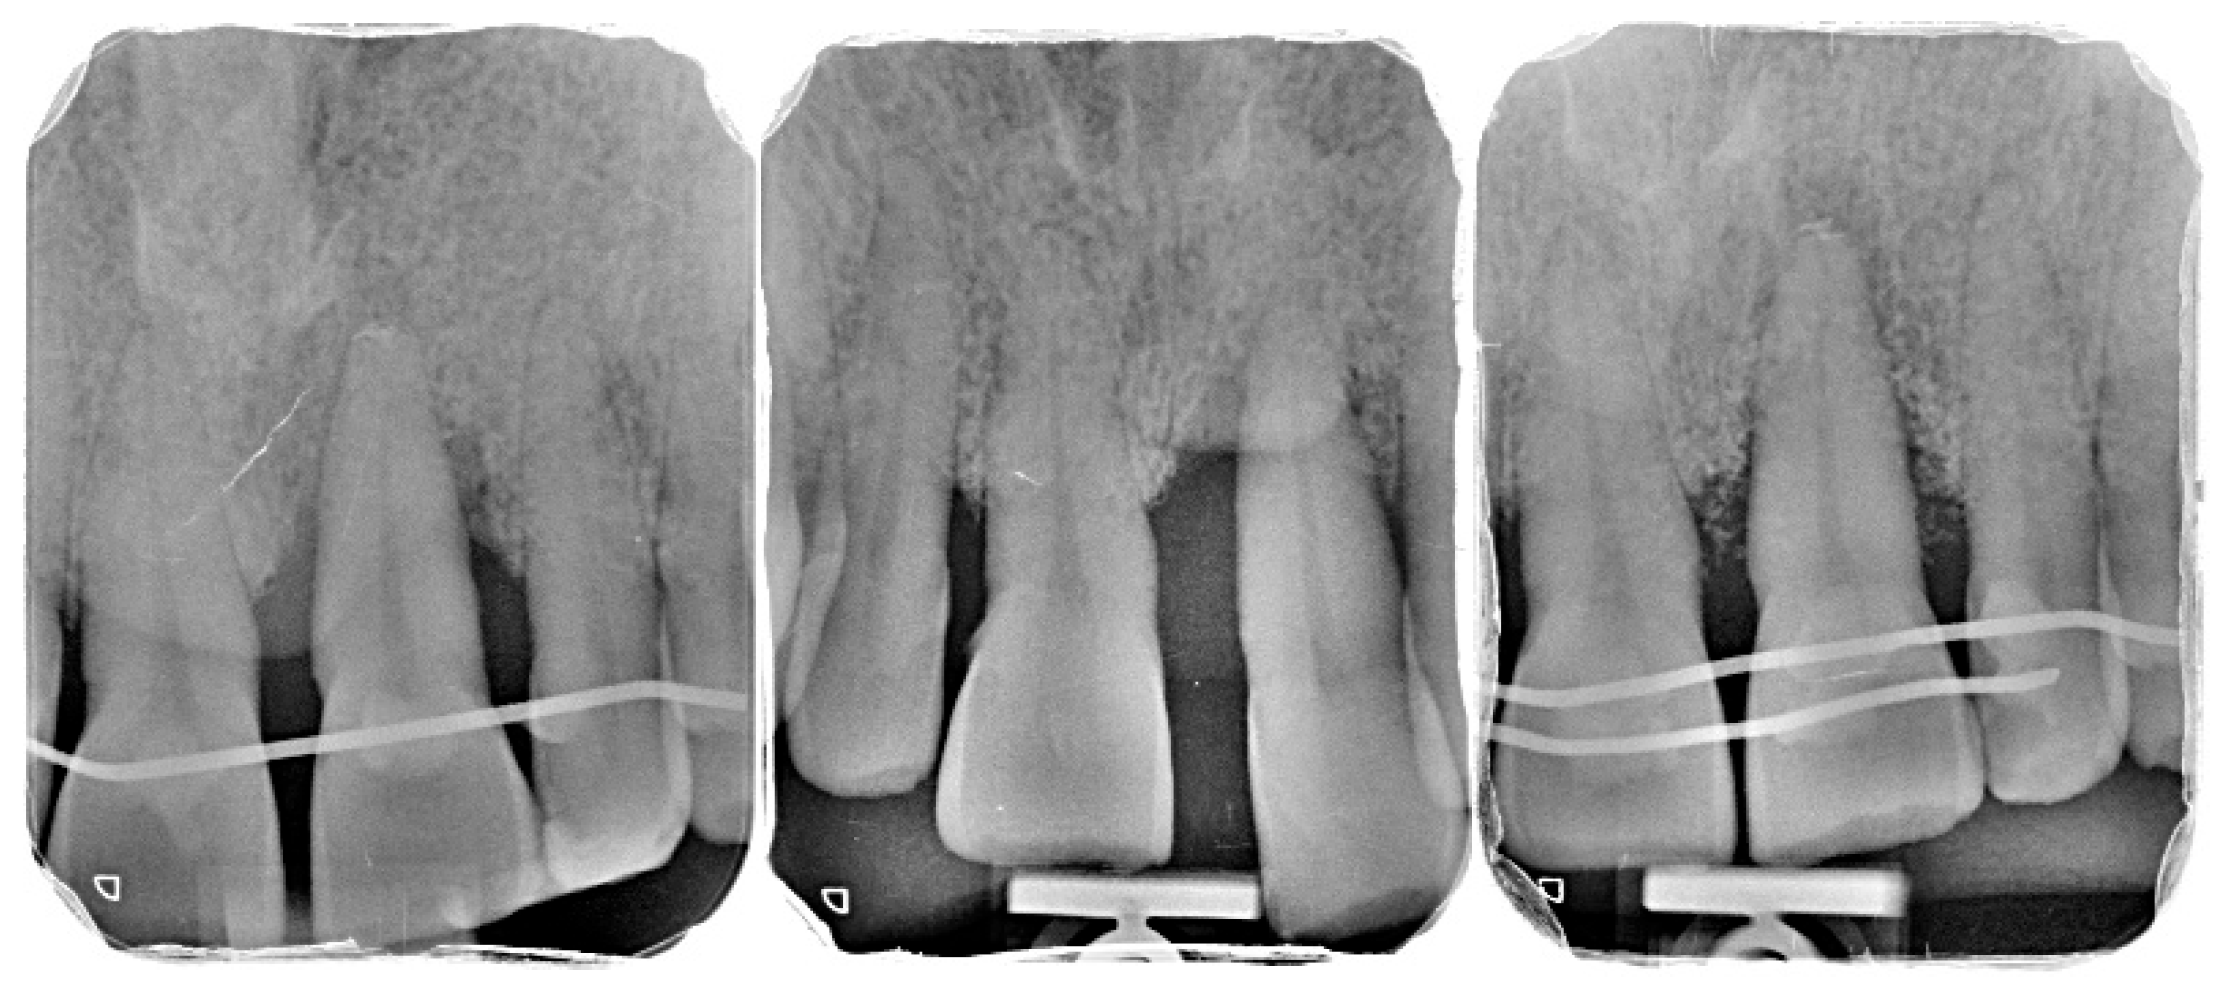

2.2. Patient Information and Periodontal Diagnosis

3.2. Radiographic Findings